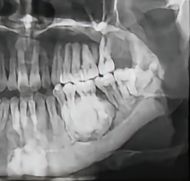

均质型成牙骨质细胞瘤

均质型成牙骨质细胞瘤由牙骨质样组织组成,常与牙根紧密相连。该肿瘤常无临床症状,或仅出现受累牙疼痛、病变区颌骨膨隆等非特异性症状